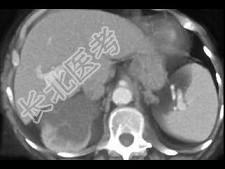

- 单项选择题根据所提供的图像,该病例最可能的诊断为 ( )

A、肾细胞癌

B、囊性肾癌

C、单纯性囊肿

D、错构瘤

E、肾血管平滑肌脂肪瘤